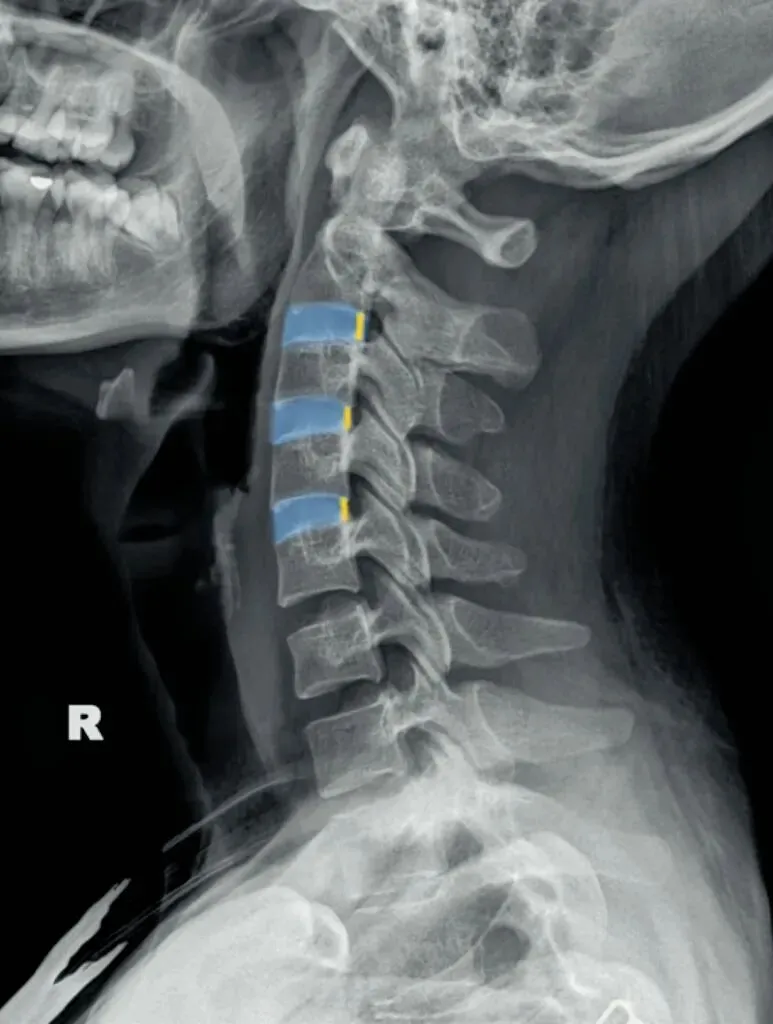

五间是指颈椎椎间隙的变化,主要在颈椎侧位片上观察椎间隙变化同时也反映了椎间盘的变化。

颈椎的退变最早发生在C56椎间盘上,因此C56椎间隙也最早发现变窄的征象。

颈椎骨性椎体为前低后高,

而椎间盘则为前高后低,因此颈椎的生理性前凸是由椎间盘的前高后低所形成的。

在正常情况下,C23、C34和C45间隙大致相等,椎间隙前部为3.8毫米正负0.5毫米,

后缘间隙为1.9毫米正负0.28毫米。

C56间隙较上为宽,而C67间隙最宽,但C7与T1间隙又较窄。